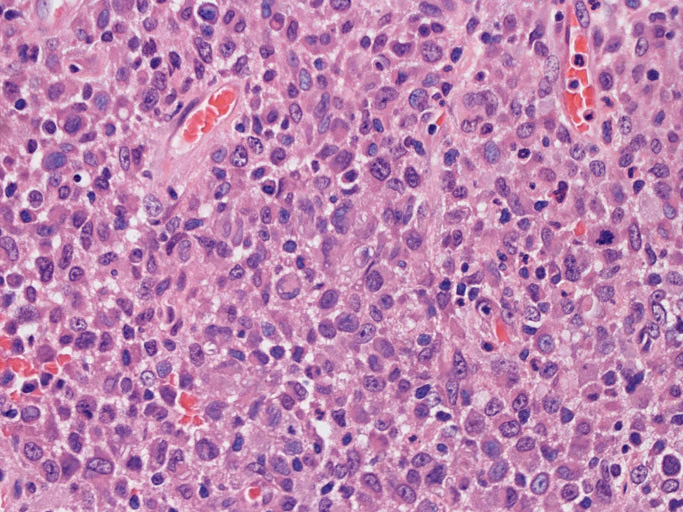

LCSの病理組織所見

Langerhans cell histiocytosisの高悪性度 variantで明らかな悪性像を示すLangerhans cellの腫瘍性増殖と定義される(WHO, 2008)

大型細胞の増殖よりなる腫瘍。縦溝,しわ,切れ込みのある核をもった大型細胞も出現する。クロマチンは顆粒状で核小体も明瞭である。核分裂は >50/10hpfと多い。eosinophilsは少ない。壊死が多発することがある。未分化ないし低分化な細胞像, 組織所見のため鑑別診断は多岐にわたり、的確な免疫染色を行う必要がある。